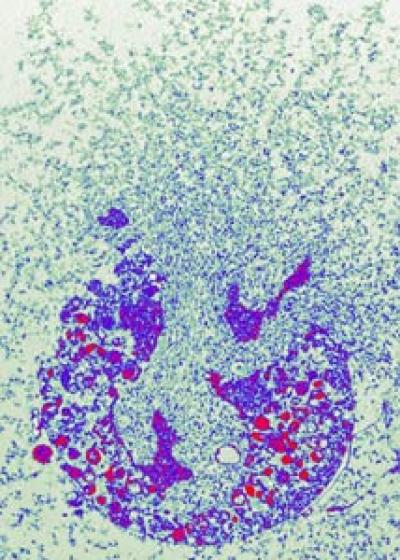

The group of scientists lead by Arturo Zychlinsky at the Max-Planck-Institute for Infectious Biology discovered a second killing mechanism: neutrophil granulocytes can form web-like structures outside the cells composed of nucleic acid and enzymes which catch bacteria and kill them. The scientists were able to generate impressive micrographs of these nets. But it remained a mystery how the granulocytes could mobilise the contents of their nuclei and catapult it out of the cells.

Only after lengthy live cell imaging and biochemical studies it became clear how neutrophils make NETs. The cells get activated by bacteria and modify the structure of their nuclei and granules, small enzyme deposits in the cytoplasm. "The nuclear membrane disintegrates, the granules dissolve, and thus the NET components can mingle inside the cells", explains Volker Brinkmann, head of the microscopy group. At the end of this process, the cell contracts until the cell membrane bursts open and quickly releases the highly active melange. Once outside the cell, it unfolds and forms the NETs which then can trap bacteria.